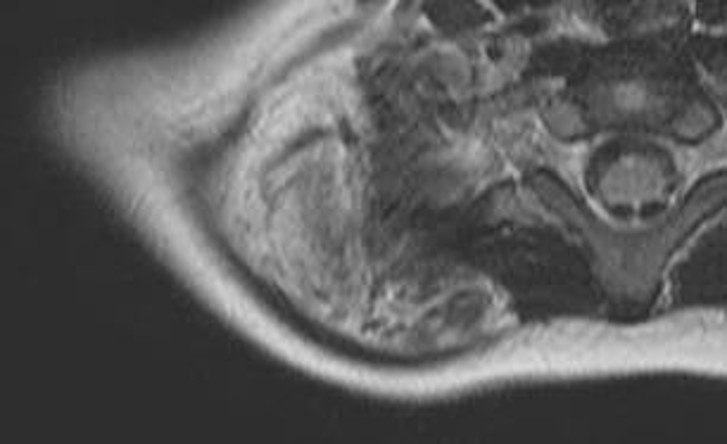

- 【参考症例】

男児

生下時からの右膝腫大

5歳:腫瘤周囲脂肪の増生と大腿四頭筋の萎縮・脂肪変性点状石灰化

15歳:大腿四頭筋腱や膝蓋腱に沿って広がる境界明瞭な腫瘤